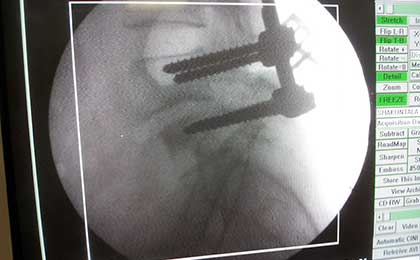

INTRA OP SPINE FIXATION

DORSAL SPINE FIXATION INTRA OP

traumatic spine fix intraop